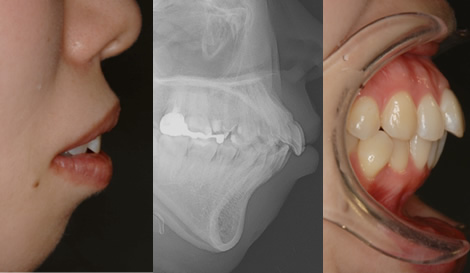

エステティックラインとは、横から見た時に鼻と顎を結んだ口元のラインのことです。

「美しい口元の基準」とも呼ばれ、矯正治療の基準になります。

このケースでは、出歯により気になるエステティックラインを、

約1年半ほどの矯正期間で改善し、美しいラインを実現しました。

見た目の美しさはもちろん、矯正によって口が閉じやすくなったことで、

鼻呼吸がしやすくなり、歯周病の予防にもつながります。